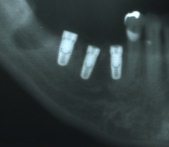

前回、皆さんはNHKクローズアップ現代を見ていかにドリリングが危険なことかがよくお分かりになったと思います。歯の中の根管治療をする時でもいきなりドリルで削ることはしませんよね。インプラントを骨に入れる時も同じだと思います。しかし従来のインプラントの埋入はすべていきなりのドリリングでおこなわれてきました。僕たちの行っている大口式、MS式インプラント埋入法は決していきなりドリリングしません。オーギュメーターやMS式オステオトームによってジグリングで広げていきます。時にはドリルを使いますが、それは最後のインプラントホールを作るときのみです。昨日のオペでもオトガイ孔付近に2本埋入しました。ベテランのインプラント専門医でもうなる位置に埋入できました。手術が終わった後患者さんの奥様は涙がぼろぼろ出てきてやっと念願の歯が入りますねと感動してました。インプラント治療はすぐれた歯科技術です。